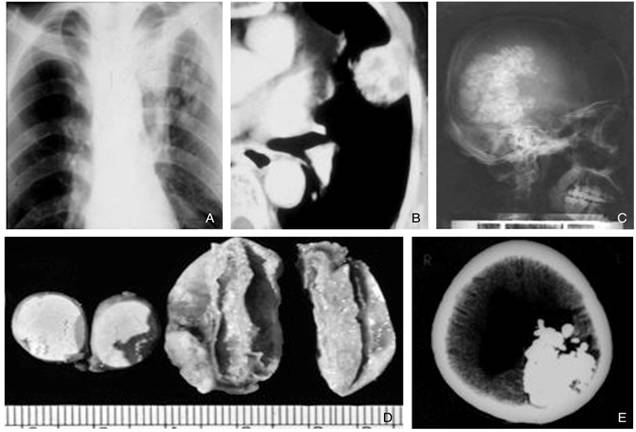

Ca bệnh thứ chín

Bệnh nhân nữ, 26 tuổi làm nghề tóc, sống tại Quy Nhơn, có triệu chứng một vết phù nhẹ từng đợt mi mắt (T) khoảng 3cm, đau nhưng không ngứa, không đỏ trong 6 tháng trước khi nhập viện. Thói quen hay ăn các loại hải sản sống cùng với mù tạt, kể cả ốc. Hai ngày trước khi nhập viện có nhức đầu nhiều, mờ mắt, song thị, buồn nôn, đại tiện phân thường, sau 24 giờ có biểu hiện rối loạn ý thức, yếu tê tay (P).

Khám lâm sàng cho thấy tri giác u ám, sụp mi (P), yếu nhẹ chi trên (P), không cứng cổ, buồn nôn, huyết áp 100/55 mmHg, mạch quay rõ 70 lần/ phút, sốt nhẹ 380C.

+ Chẩn đoán sơ bộ: Theo dõi Viêm não màng não do virus.

+ Xét nghiệm cận lâm sàng:

·Công thức máu toàn phần có tăng bạch cầu chung lên đến 14.000, trong đó BCAT chiếm ưu thế 35,6%, glucose và protein máu máu bình thường, bilan gan mật, lipid trong giới hạn;

·X-quang phổi và siêu âm bụng không bất thường, ngoại trừ có sỏi nhỏ thận (P);

·Dịch não tủy cho dịch trong suốt, hơi vàng, không thấy vi khuẩn và chỉ số bạch cầu tăng cao 27.9%.

·Tuy nhiên, sau 38 giờ kể từ khi nhập viện bệnh nhân mất ý thức à chuyển sang chẩn đoán bệnh do ký sinh trùng, xét nghiệm 6 loại giun sán, kết quả dương tính với G. spinigerum 1/3200

à Chuyển điều trị hồi sức tích cực, chụp CT-scanner cho hình ảnh phù não nhẹ, hình ảnh di chuyển và giống calci hóa tại hai bán cầu. Phác đồ thuốc lựa chọn [albendazole + dexamethason + hydrocortison + kháng sinh phổ rộng], bệnh nhân tỉnh táo sau 14 ngày và hồi phục hoàn toàn sau 5 tháng kể từ khi điều trị.

H10